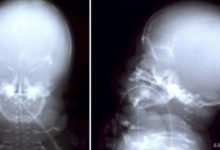

Bazı kritik KKH’ler, gelişmekte olan bebeğin kalbinin resimlerini oluşturan fetal ekokardiyografi adı verilen özel bir ultrason türü kullanılarak gebelik sırasında teşhis edilebilir. Ancak hamilelik sırasında bazı kalp kusurlarına rastlanmaz. Bu durumlarda kalp kusurları doğumda veya çocuk büyüdükçe tespit edilebilir.